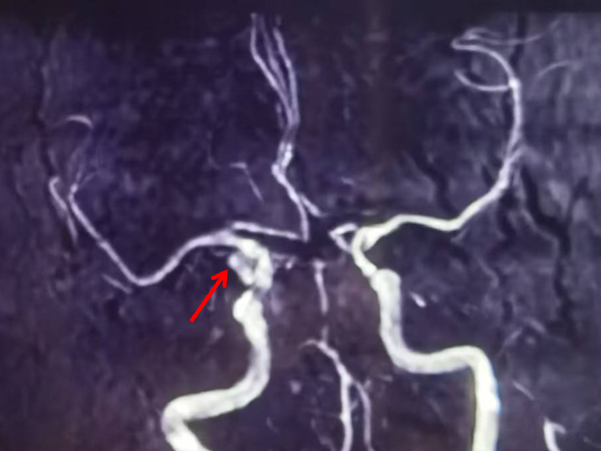

颅脑MRA(当地医院):左侧颈内动脉后交通段局部膨大,可疑动脉瘤。

左侧颈动脉正侧位造影:左侧颈内动脉后交通段动脉瘤(箭头所示)。

左侧颈内动脉3D造影可见动脉瘤位于后交通动脉起始处。

3D血管造影可见左侧后交通动脉瘤,大小约7.05×7.47mm,瘤颈3.68mm,考虑胚胎型大脑后动脉。